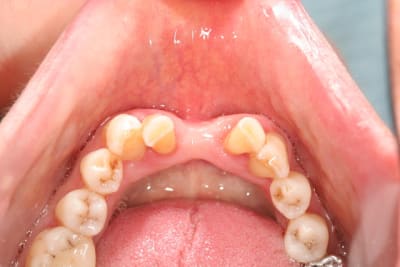

et ici ?? vous feriez quoi ?

32 et 42 pas mobiles

malheureusement, l'espace est réduit pour mettre deux implants.

comment avez vous déjà géré ce type de cas ??

le haut est déjà traité...

à propos du cas , j'ai vu avec la patiente cet aprem; nous avons décidé de faire un petit bridge provisoire de quelques mois et si (après traitement paro bien sure) les dents ne sont pas mobiles, on passera au bridge définitif. sinon, ce sera pose de deux implants en position 42-32 pour éviter une greffe que la patiente refuse.